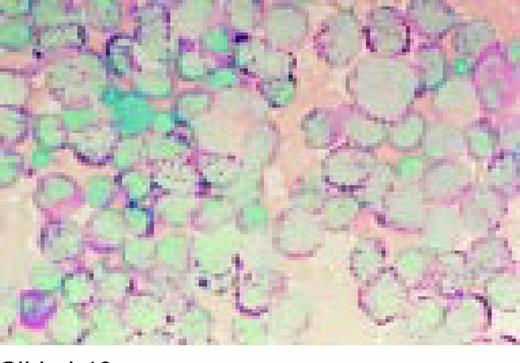

Slide L10

Acute lymphoblastic leukemia, FAB classification L2, bone marrow aspirate, periodic acid-Schiff stain (PAS). The coarse granularity in the cytoplasm as well as some frank cytoplasmic globules are characteristic of the PAS reaction when it is positive in lymphoblasts.FIG10